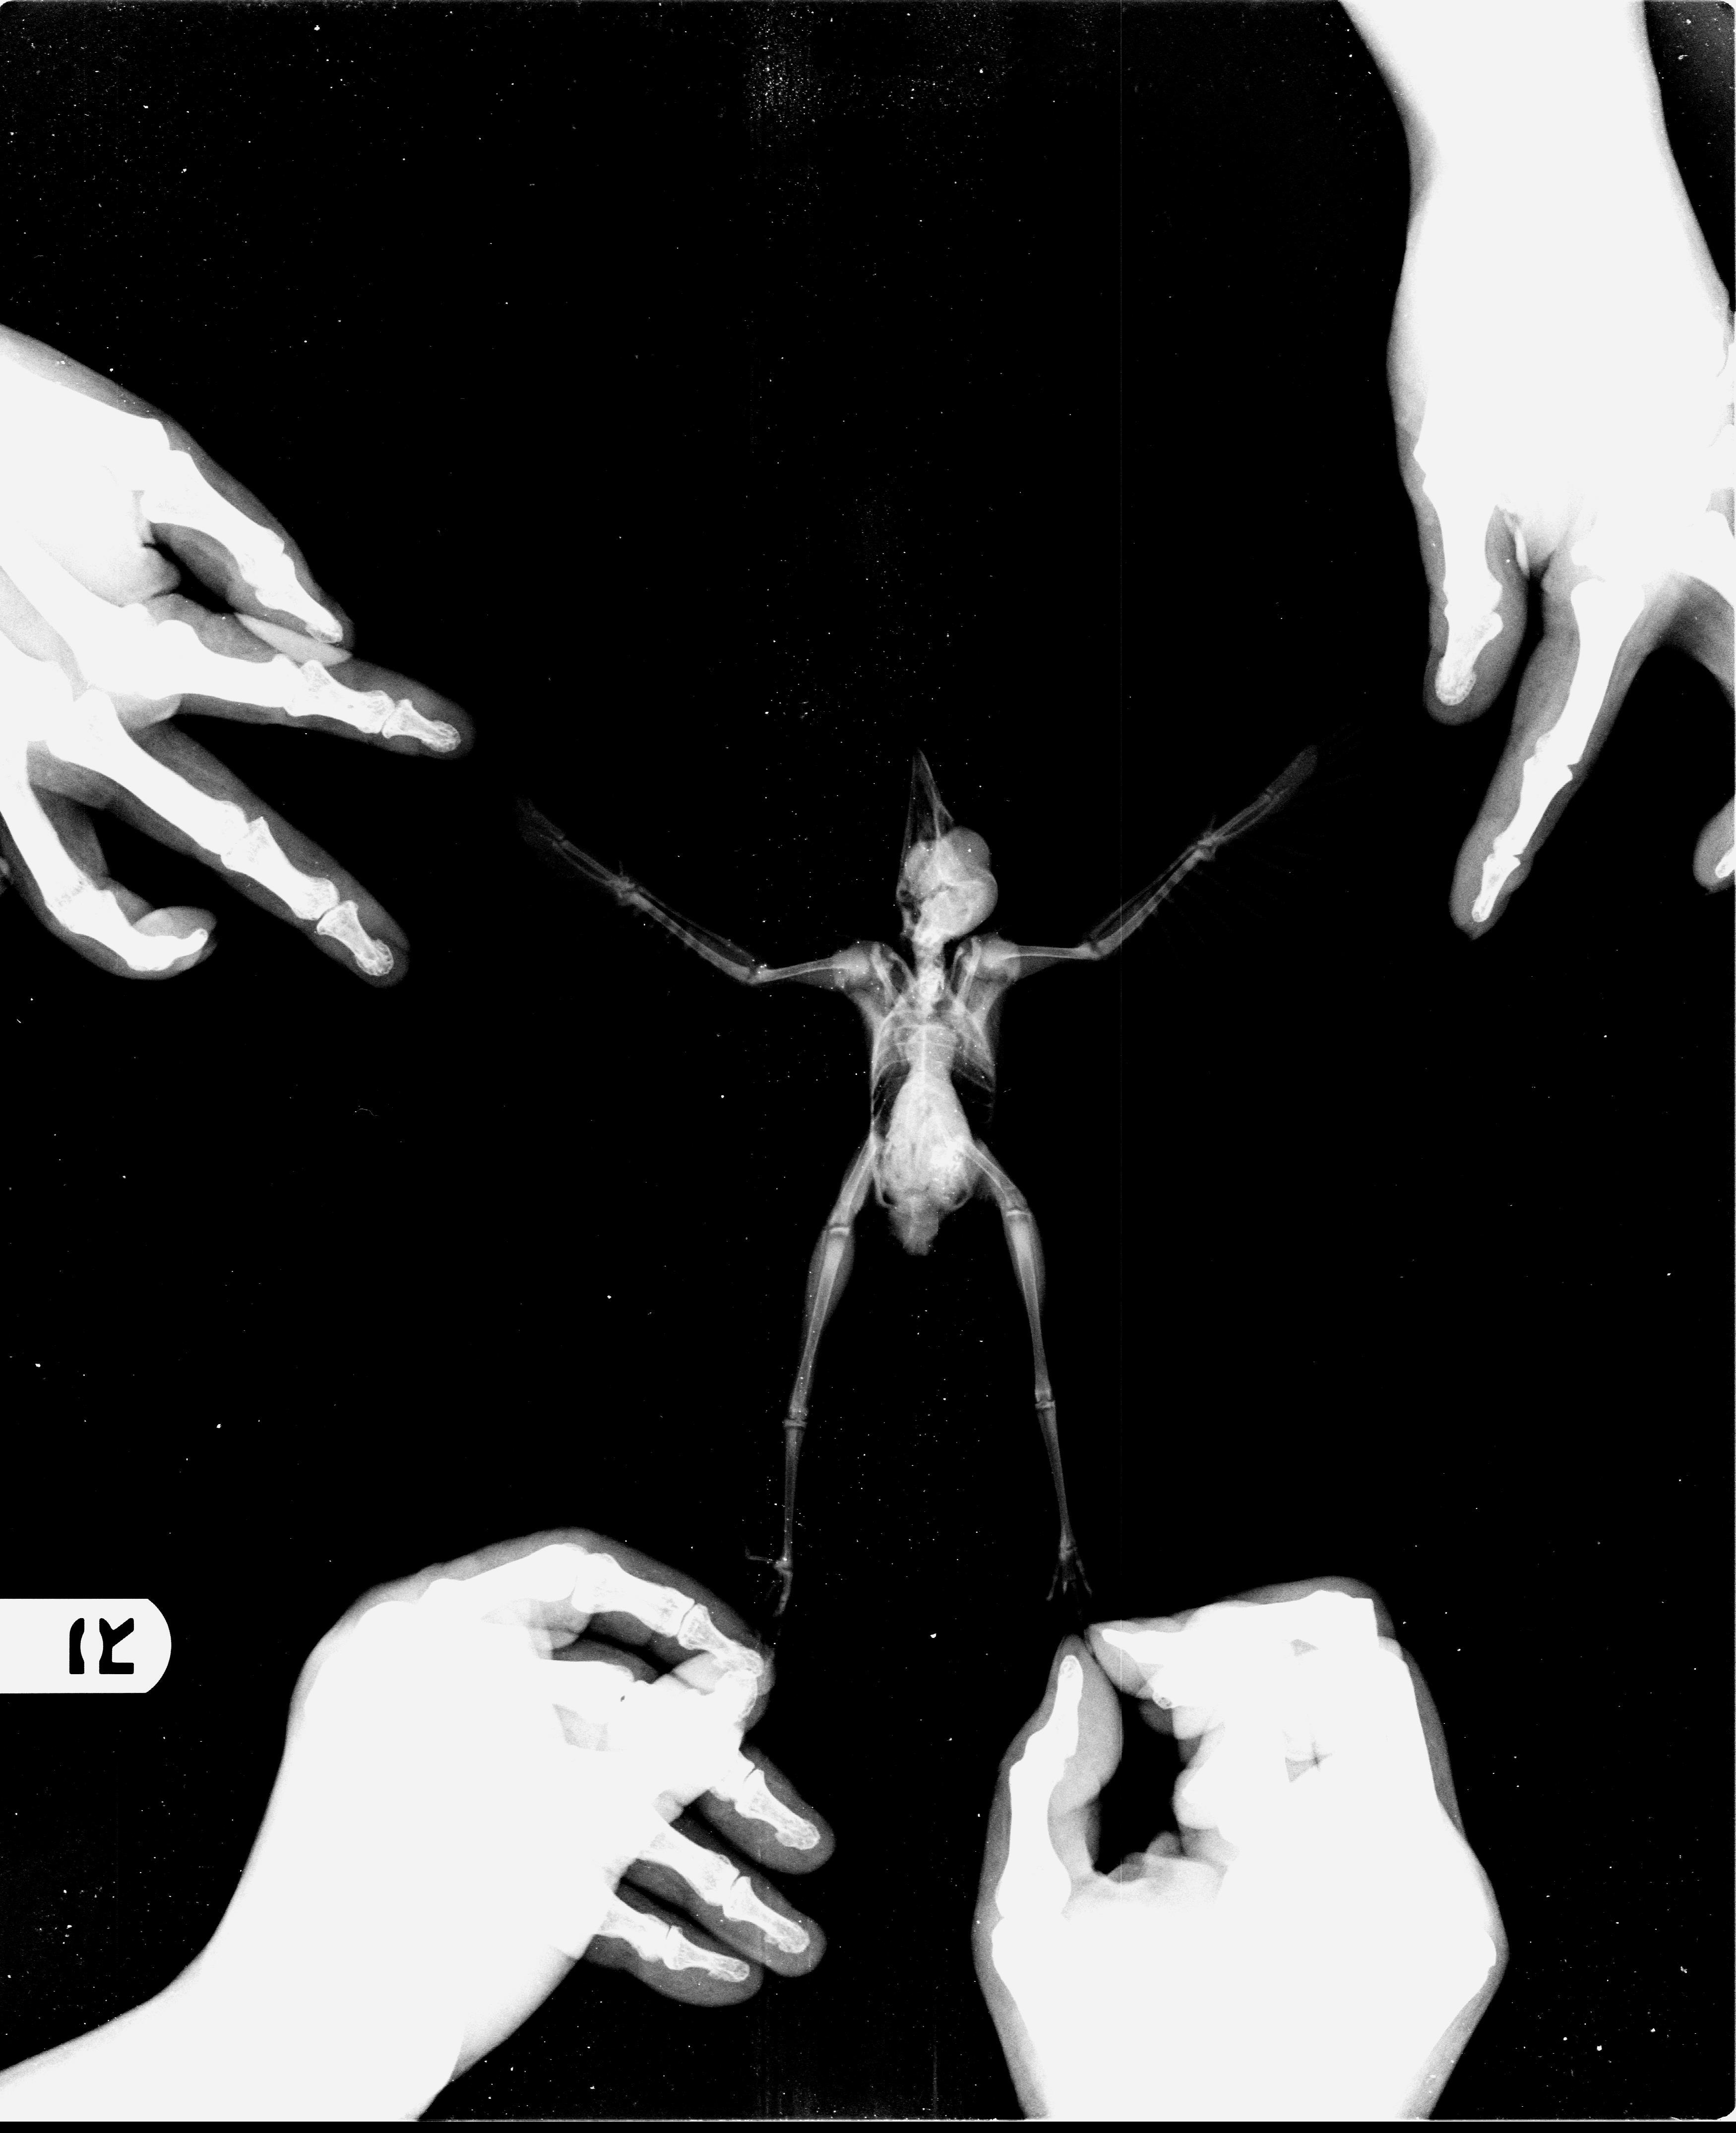

조류 엑스레이(X-Ray) 정상사진 작성자가람캡틴|작성시간22.04.25|조회수51 목록 댓글 0 글자크기 작게가 글자크기 크게가 다음검색 현재 게시글 추가 기능 열기 북마크 공유하기 신고 센터로 신고 댓글 댓글 0 댓글쓰기 답글쓰기 댓글 리스트